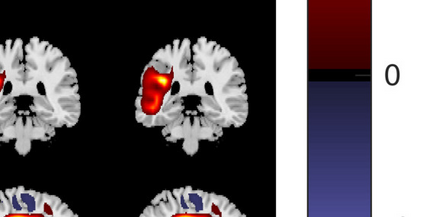

In the last two decades, unsupervised latent variable models---blind source separation (BSS) especially---have enjoyed a strong reputation for the interpretable features they produce. Seldom do these models combine the rich diversity of information available in multiple datasets. Multidatasets, on the other hand, yield joint solutions otherwise unavailable in isolation, with a potential for pivotal insights into complex systems. To take advantage of the complex multidimensional subspace structures that capture underlying modes of shared and unique variability across and within datasets, we present a direct, principled approach to multidataset combination. We design a new method called multidataset independent subspace analysis (MISA) that leverages joint information from multiple heterogeneous datasets in a flexible and synergistic fashion. Methodological innovations exploiting the Kotz distribution for subspace modeling in conjunction with a novel combinatorial optimization for evasion of local minima enable MISA to produce a robust generalization of independent component analysis (ICA), independent vector analysis (IVA), and independent subspace analysis (ISA) in a single unified model. We highlight the utility of MISA for multimodal information fusion, including sample-poor regimes and low signal-to-noise ratio scenarios, promoting novel applications in both unimodal and multimodal brain imaging data.